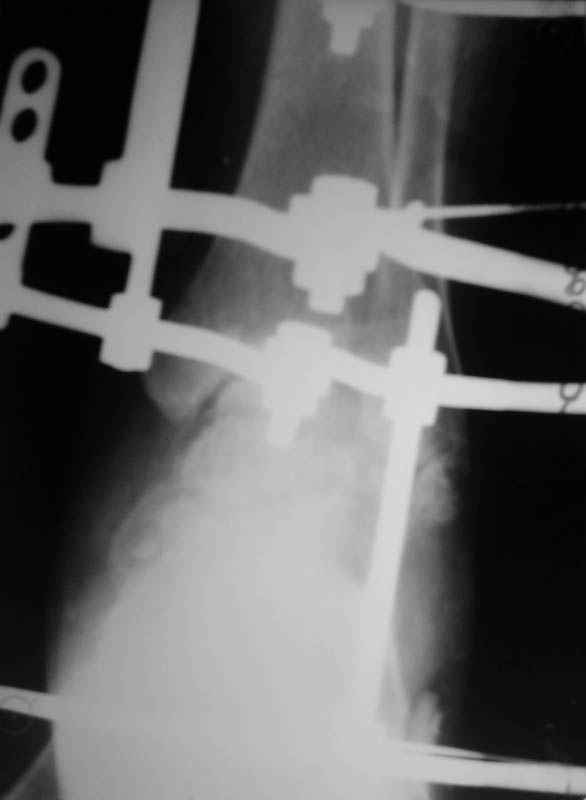

Диагноз: закрытый переломо-вывих таранной кости, двухлодыжечный перелом, подтаранный вывих стопы, асептические некрозы. Перелом был закрытый, но были некрозы из-за давления отломков (см.фото).

Что сделали. Под наркозом попытка закрытой ручной репозиции - безуспешно. Латеральный доступ, открытая репозиция таранной кости. Наложение АВФ (2 кольца, 2 полукольца на пятке и переднем отделе стопы). Устранение подтаранного вывиха стопы. Послеоперационные снимки в приложении.